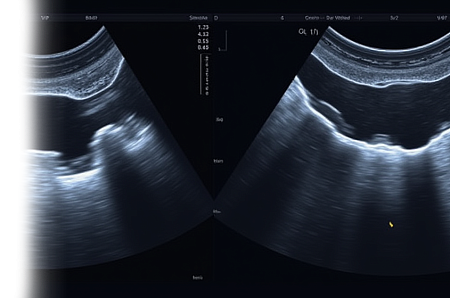

Ультразвуковое исследование - самый современный, безболезненный, достоверный и широко используемый метод диагностики заболеваний. При данном исследовании отсутствует лучевая нагрузка, поэтому он безболезненный и безопасный, не требующий применения контрастных веществ, легкодоступный, многофункциональный и быстрый способ проведения процедуры.

Суть метода ультразвукового исследования базируется на способности ультразвука отражаться от внутренних органов и тканей разной плотности, и переводить изображение на монитор.

Ультразвуковое исследование является важным инструментов в диагностике различных заболеваний и патологий. Благодаря своей эффективности и доступности, оно широко используется в медицинской практике и помогает специалистам быстро и точно поставить диагноз.